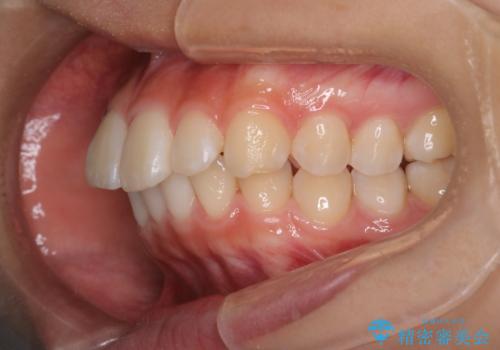

裏側矯正で口元をすっきりとした印象へ!

- 出っ歯を治したいとのことで来院されました。

目立たない装置が希望とのことでハーフリンガルで治療をすることとしました。